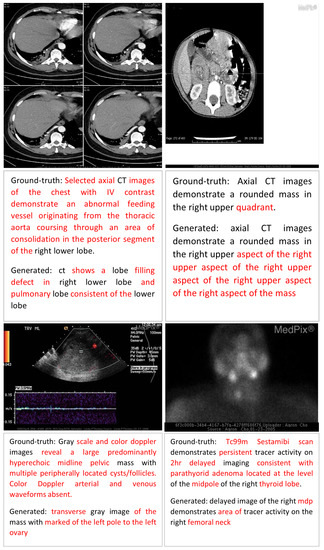

Error Analysis